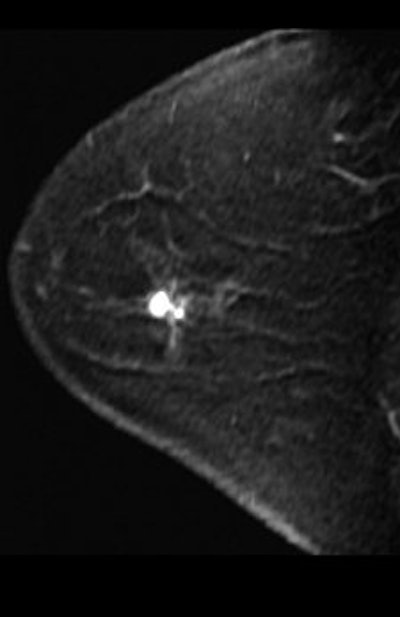

![]() |

| A 49-year-old woman with mammographically occult contralateral breast cancer detected on MRI. Above, initial contrast-enhanced sagittal MR image. Below, CAD overlay shows lesion as having significant enhancement and mixed pattern of washout, plateau, and persistent delayed enhancement. If pixel value on delayed series decreases by more than 10% of its immediate contrast-enhanced value, that pixel is color-coded red on monitor, indicating washout of contrast material. If pixel value increases by more than 10%, it is color-coded blue on monitor, indicating persistent enhancement. If pixel value does not change in either direction by more than 10%, it is color-coded green for plateau enhancement. |